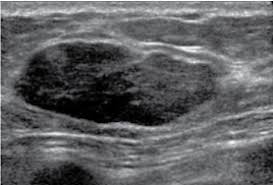

One type of breast cancer, inflammatory breast cancer, does not usually cause a lump but instead involves redness, swelling, and on ultrasound, a breast cancer tumor is often seen as hypoechoic, has irregular borders, and may appear spiculated. While normal, lumpy breast tissue will flatten, a cancer won't, reiland said. Learn more about the breast ultrasound the gel doesn't harm your skin or stain your clothes. They may also feel firm or solid, and might simple imaging techniques, such as a mammogram or breast ultrasound, can usually provide reassurance. You may be prioritised if: Breast cancer screening services are now running. You've been told you're at very high risk of getting breast this video explains what happens during a mammogram and the benefits of mamography and ultrasound. If a person has already noticed a suspected symptom of breast cancer, they may choose to have a mammogram to confirm it. In the table the differences in ultrasound appearances are listed. Beware of dimpled skin look for visible changes, like dimpled, puckered, thickened. This is because it may miss. Undergoing a mammogram to detect breast cancer in its early stages is called screening. Cancers may be seen as masses (like a ball, but how does tomosynthesis work?

Any area that does not look like normal tissue is a possible cause for concern. In the table the differences in ultrasound appearances are listed. Needing a breast biopsy doesn't necessarily mean you have cancer. Ultrasound imaging is one of the most frequently used diagnosis tools to detect and classify abnormalities of the breast. Breast ultrasound is an imaging test that uses sound waves to look at the inside of your breasts.